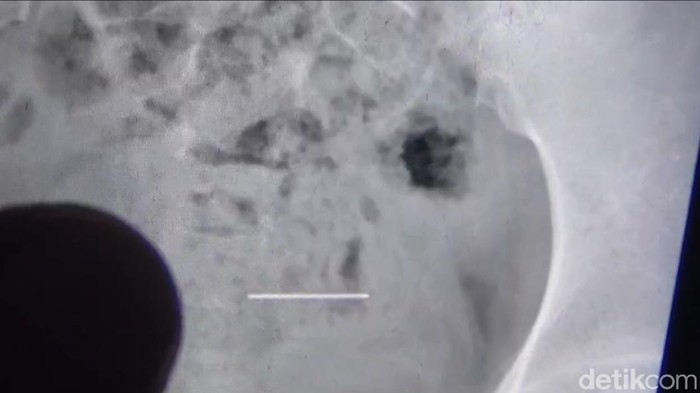

Berdasarkan hasil rontgen, jarum pentul tersebut diketahui sudah berada di bagian bawah saluran pencernaan. Tim medis memilih penanganan konservatif dengan pemberian obat untuk memperlancar pencernaan agar jarum dapat keluar secara alami melalui buang air besar (BAB).

"Posisi jarum sudah di saluran pencernaan bagian bawah. Kami memberikan obat untuk memperlancar pencernaan agar jarum bisa keluar secara alami. Harapan kami jarum tersebut bisa keluar saat buang air besar," tuturnya.